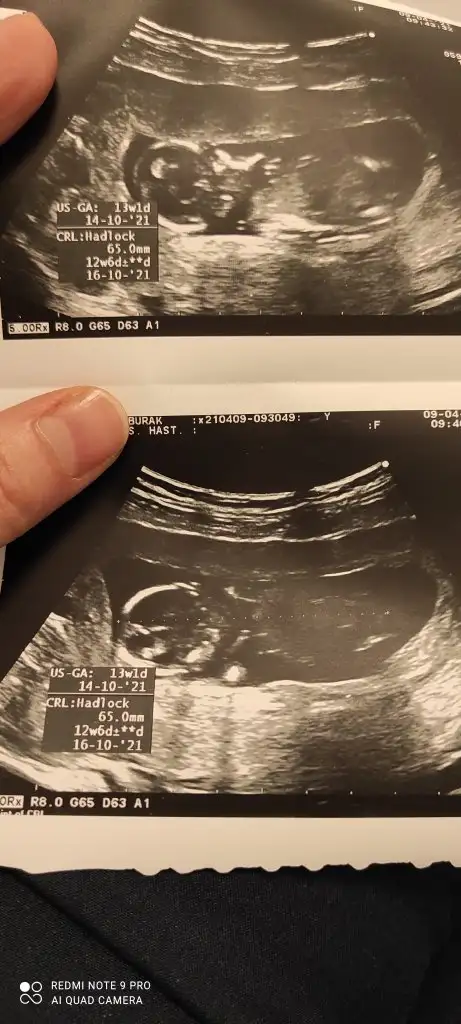

dr soylemeden siz gorun genital nub teorisi ( bebegin cinsiyeti)

Ikra meyra Ikra meyra 12+1 sata göre bana da bakar mısınız çok hareketli oldugu için bişey demedi Dr

• IMG_20210409_103239.webp

IMG_20210409_103239.webp

30,5 KB · Görüntüleme: 78